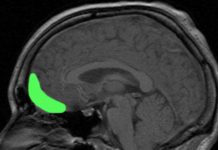

Risky Behavior Tied to Two Key Brain Regions

The study, assessing risk-and-reward behavior among rats, may provide clues as to why some people prefer to live a steady, predictable life while others are more prone to taking chances.